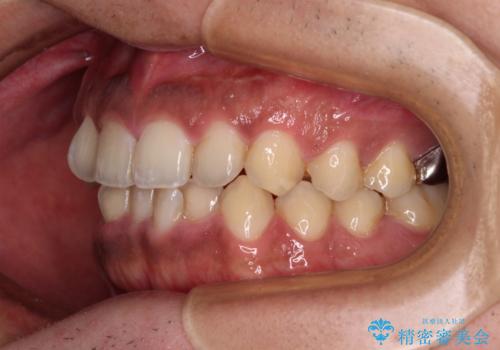

- 前歯のデコボコを気にして来院された患者様です。

前歯が90度近く捻れていたため、しっかりと治すことを考えるとワイヤー矯正の方がおすすめではありましたが、本人の希望によりインビザラインを用いて矯正治療を行うこととしました。

インビザラインは、十分な装着時間が達成されると前歯のデコボコをしっかりと改善できますが、1日の装着時間が20時間に達しなくなると、不十分な仕上がりとなるため、しっかりと装着するよう指示をしました。

途中2年強の来院がなく、改善されていたデコボコが元に戻ったり、装着時間が不足しており前歯のデコボコは十分に改善することはできませんでしたが、5年間の有効期限内で可能な限り歯列を整えることができました。